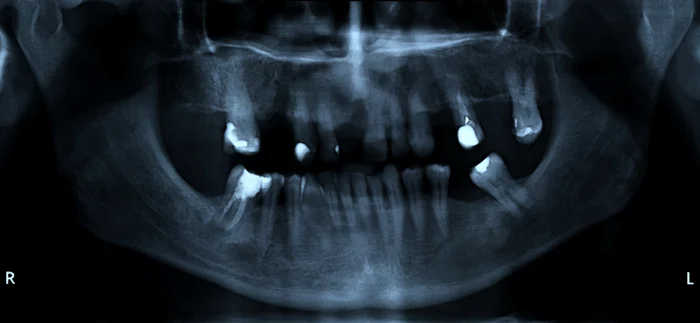

Prea multe radiografii dentare pot crește riscurile pentru sănătate. Foto: Shutterstock.